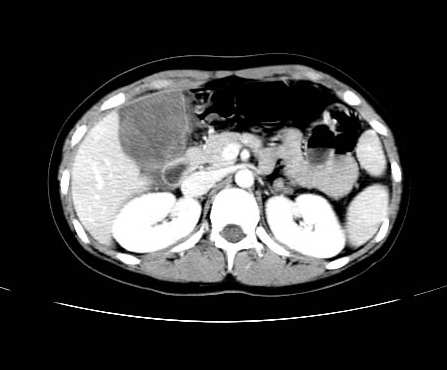

女 16岁  右上腹痛一天,无其他不适

肿块最大径位于十二指肠降段与水平段移行处,并且与肝脏压迹呈“0”形征,可以考虑位于肝外并与胃肠道关系紧密,考虑胃肠道间质瘤(gist)可能较大,须除外神经节起源肿瘤。

肿块与十二指肠关系密切,支持间质瘤诊断.肝脏与结肠均为受压改变.

右下腹巨大肿快,密度不均匀,内见坏死低密度区,边界清楚,与周边胀器明显有分界,未见强化,多考虑来源于间叶组织的良性肿物.

病灶巨大,少部分向肠腔内生长,大部分向长腔外生长。其密度不均匀,增强显示明显不均匀强化,并见有大片状始终不强化的不规则坏死液化区。虽然病灶中上部形态尚可,病人又如此年轻,但中下部形态、密度、强化特点强烈提示为恶性病灶。综上,我考虑本病例为:恶性胃肠道间质瘤。